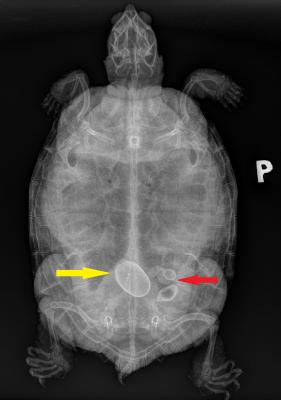

Po základním klinickém vyšetření bylo provedeno rentgenologické vyšetření, které odhalilo výrazné problémy ve vejcovodech.Žlutá šipka ukazuje na vejce, které má sice fyziologickou velikost, ale skořápka vykazuje výrazné patologické znaky (nadměrné ukládání vápníku, přičemž vejce želvy nádherné mají mít kožovitou skořápku).

Červená šipka ukazuje na deformované zárodky vajec, které jsou však také zvápenatělé a tedy už neporostou.